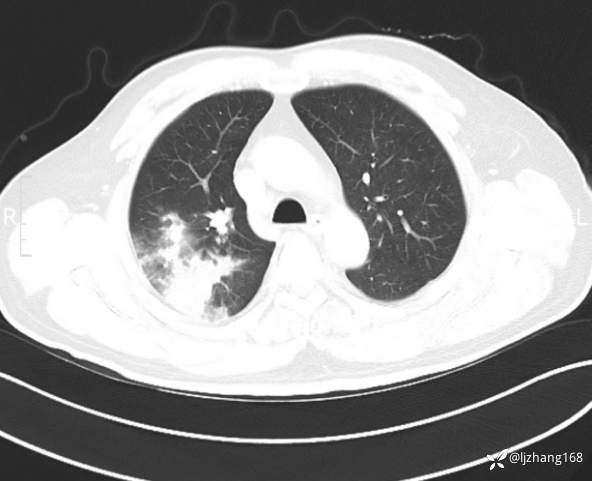

中年男患,右肺团片影,炎症0R肿瘤?

简要病史: 20+天前患者因受凉后出现阵发性咳嗽,咳少量白色粘痰,痰易咳出,伴活动后气短,伴纳差、乏力、全身酸痛,伴多汗,无痰中带血及咯血,无发热、畏寒及寒战,无潮热、盗汗,无夜间阵发性呼吸困难及端坐呼吸,无声嘶,无头晕、头痛,无黑矇、晕厥及意识障碍,无腹痛、呕血及黑便等不适,遂就诊于当地医院予以输液等治疗后未见明显好转(具体诊疗不详),现为进一步诊治就诊于我院门诊,以“右肺占位”收入我科。病来饮食欠佳,近期体重下降(具体不详)。既往糖尿病病史7+年,未规律监测血糖,血糖控制不佳。否认“高血压、冠心病及慢性肾脏病”等慢性疾病史。否认“肝炎、结核、伤寒”等传染病史。否认食物、药物过敏史。否认外伤、输血史,预防接种史不详。

辅助检查:糖化血红蛋白12.3%。肺炎支原体IgG、IgM、呼吸道合胞病毒均未见明显异常。胸部CT:右肺上叶阻塞性肺炎。